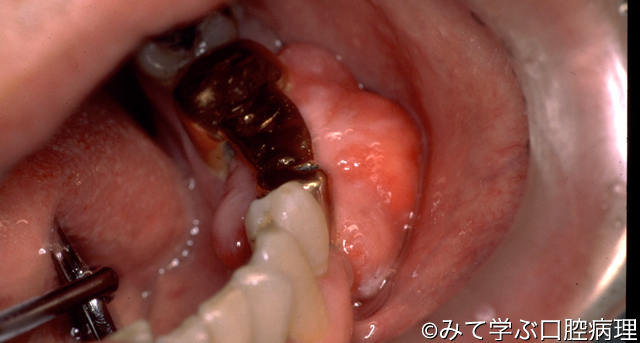

肉芽腫性エプーリス

小臼歯から大臼歯相当部の頬側歯肉に有茎性の腫瘤がみえる

腫瘤は表面は平滑であるが凹凸不整にみえる